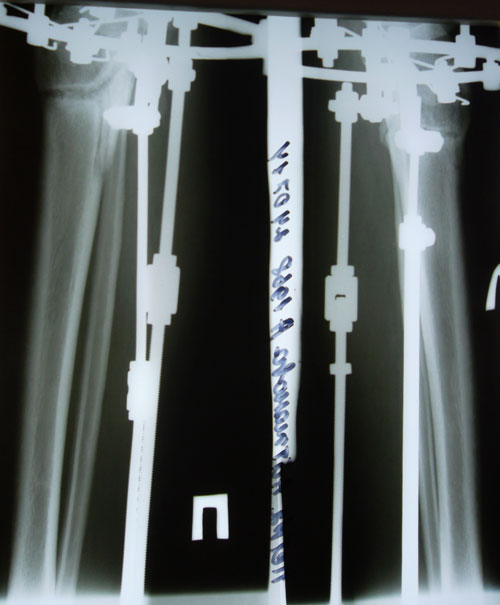

рентген от 24.07.2014г.

Здравствуйте, А.! По результатам рентгена: сращение хорошее, но: если Вас ничего не беспокоит, то Н.Н. советует ещё походить до 18 августа, учитывая возраст и степень деформации. После 18.08. ждём на снятие аппаратов (дату приезда сообщите, планируйте приезд в будние дни).

Дата операции 18.03.2014г.

Дата снятия аппаратов 21.08.2014г.

Срок лечения 5 месяцев.